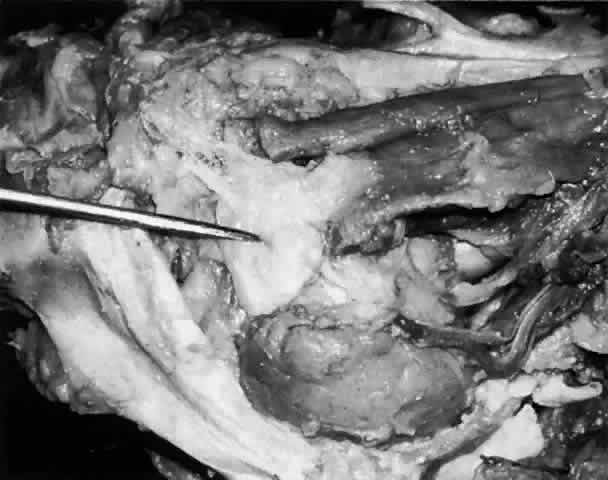

The main lacrimal gland resides in the superotemporal orbit, partially within a shallow bony fossa in the lateral angular process of the frontal bone (fossa glandula lacrimalis). The gland is situated between the eyeball below and the curved orbital wall above, giving it a somewhat compressed and curved shape. It may extend inferiorly to the lateral canthal tendon. The lateral horn of the levator aponeurosis crosses the gland anteriorly, separating it into a larger superior or orbital lobe and a smaller inferior or palpebral lobe (Fig. 2). The division is incomplete because the larger orbital lobe is connected to the smaller palpebral lobe posteriorly by a bridge of glandular tissue, draining tubules, and Müller's muscle, which is attached to the underside of the levator muscle and aponeurosis. The lacrimal gland is surrounded by fibrous tissue that is attached superiorly to the periosteum of the frontal bone and inferiorly to the orbital portion of the zygomatic bone.1

Fig. 2. With the roof and lateral wall of the left orbit removed, this cadaver dissection demonstrates the orbital lobe (black arrow) and the palpebral lobe (white arrow) separated by the lateral horn of the levator aponeurosis (pointer).

These attachments may become attenuated in older persons, allowing the gland to herniate through a weakened orbital septum to give a temporal bulge in the upper eyelid (Fig. 3). The lacrimal gland tissue is usually grayer and pinker than the surrounding yellow adipose tissue.